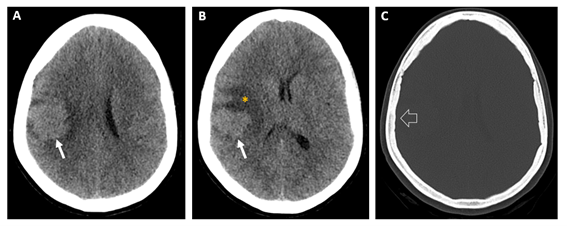

Caso del mes Noviembre 2025

Autor/Autores

Sara Septién Rivera; Josep Castell Aulet; Mildred Viveros Castaño. Área de Neurorradiología, Hospital Universitario de Bellvitge, Barcelona, España Mail: sseptien@bellvitgehospital.cat